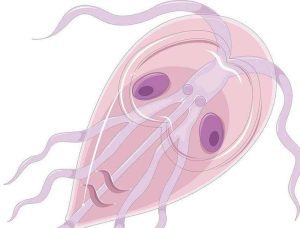

Giardia intestinalis

Giardia sa typicky vyskytuje v kontaminovanej vode, z ktorej sa napijete. Lokalizuje sa v tenkom čreve, s ktorým súvisia aj problémy, ktoré vás postretnú. Najčastejšie vás potrápi hnačka a zvracanie, to neznie tak zle, že? Ale trvať to môže aj vyše týždňa.